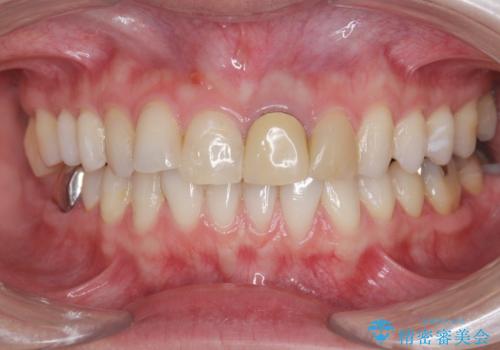

前歯の見た目を改善 セラミック審美治療

- 長年気になっている前歯の見た目を改善したいと来院されました。

両側の前歯に根尖性歯周炎を認めたため根管治療を行ったのち、ジルコニアクラウンを用いた審美性の改善を計画します。

前歯の見た目が改善したことで長年の悩みが解決できた。と治療内容に満足いただくことができました。